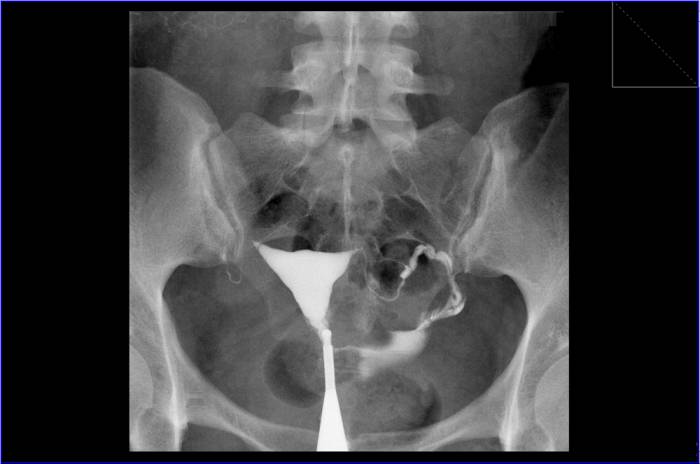

Снимки гистеросальпингографии

Правая маточная труба в ампуле непроходима.

Левая маточная труба свободно проходима.

Буква «R» на изображении указывает на правую сторону пациента.

Стрелкой показано препятствие в ампулярном отделе правой маточной трубы.